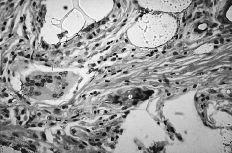

ABFigura 3. Aspecto microscópico. A: Sinovitis hipertrófica con granulomas por silicona (HE, 40*). B: Reacción de células gigantes a cuerpo extraño (HE, 250*).

Debido a esta falta del implante hemos observado en un 20% de los casos luxación y subluxación de la artroplastia, en un 30% inestabilidad en DISI y en un 10% en VISI. La incidencia de imágenes líticas intraóseas y sinovitis por liberación de partículas de silicona en nuestra serie es del 40%. Surgen por la abrasión y el desgaste del implante y producen una sinovitis hipertrófica con granulomas por silicona.19 Microscópicamente se aprecia la respuesta del huésped a estas partículas como una reacción de células gigantes a cuerpo extraño. Los leucocitos y macrófagos fagocitan el material, pero la silicona no se afecta por las enzimas lisosomales, lo que induce una sinovitis reactiva que no es exclusiva de la silicona (PMMA, polietileno y otros materiales metálicos), estando siempre en relación con el tamaño de la partícula. Las partículas de silicona son de 30 a 60 micras de diámetro. Estos implantes se han desaconsejado para la sustitución del escafoides y del semilunar, ya que al estar sometidos a importantes cargas de compresión se produce su fragmentación.31 Los factores que desgastan el implante de silicona y contribuyen a la formación de partículas son las fuerzas excesivas a través del implante debidas a la asociación de inestabilidad o de colapso, una malposición o exceso de tamaño, exceso de movilidad y abuso de la actividad diaria.43,44